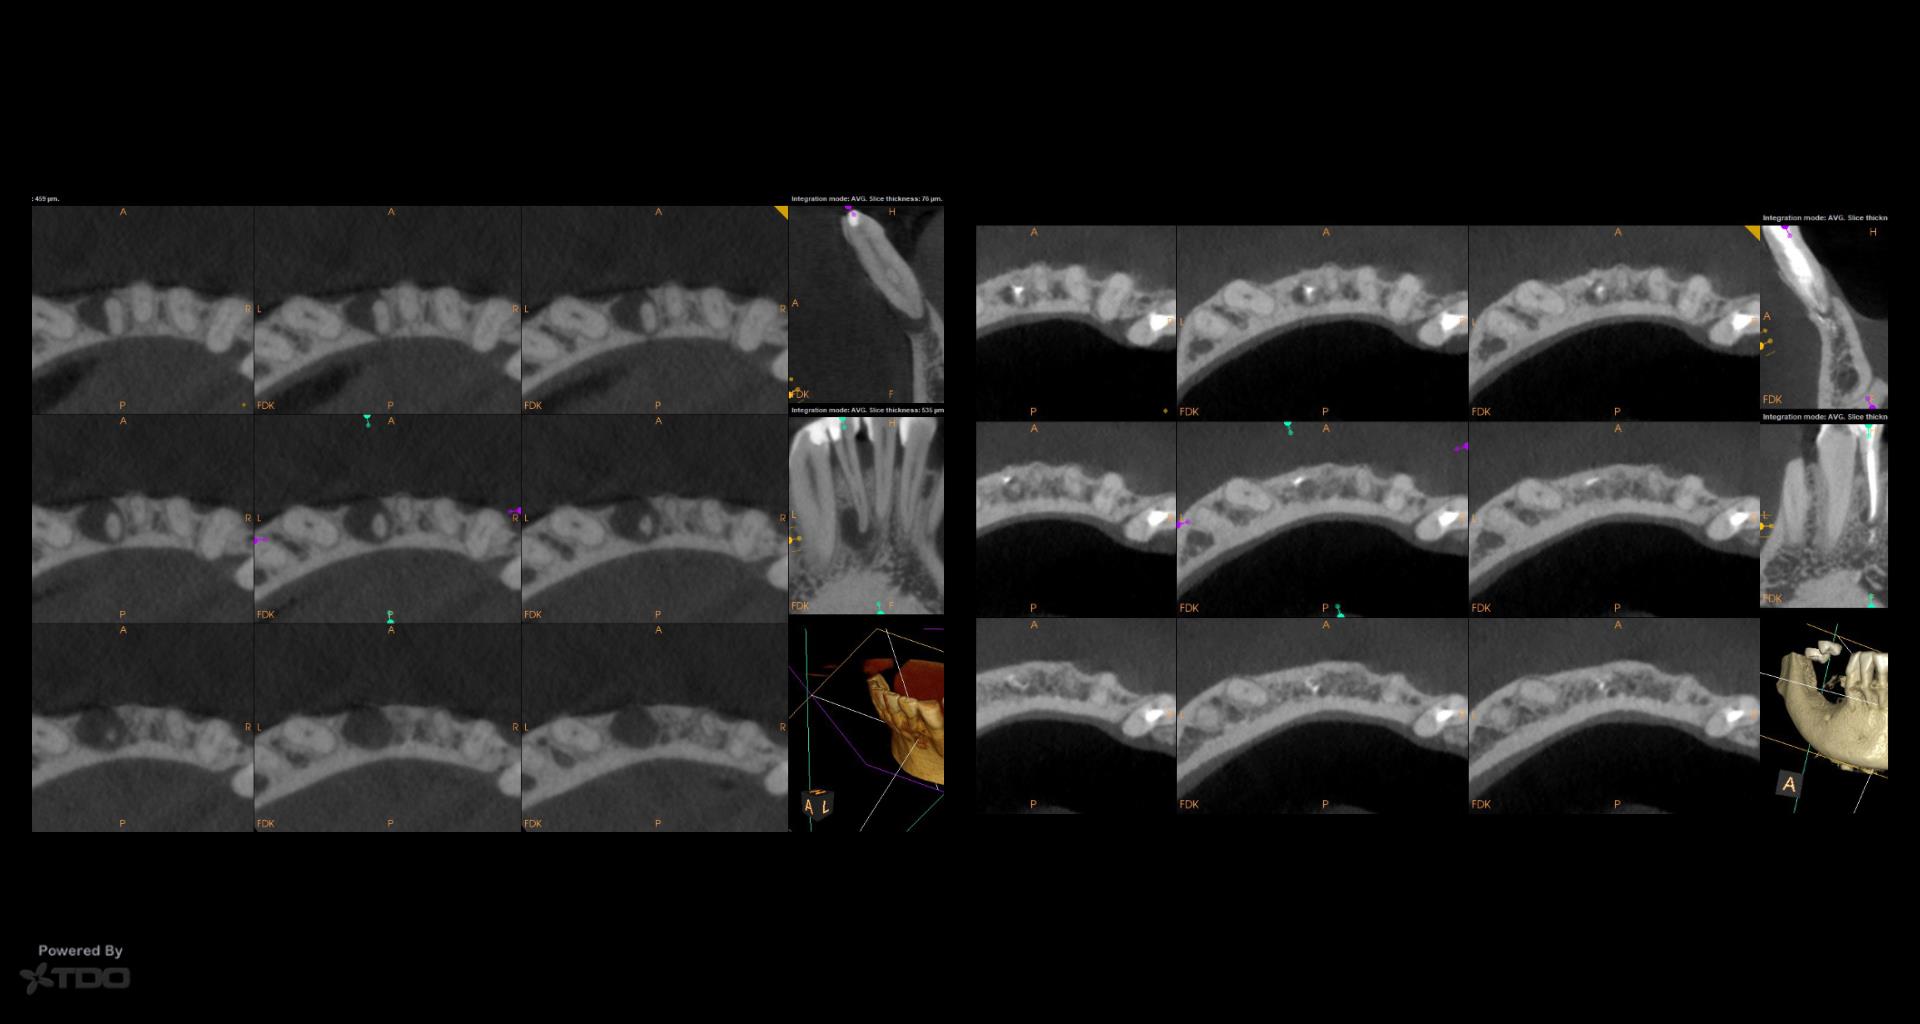

It’s a little embarrassing…but I have been treating a tooth of Joy’s for 5 years….Multiple CaOH visits over those 5 years. Coulod never get the area to resolve. Finally tried a GW on it…..1 yr recall today. gbc